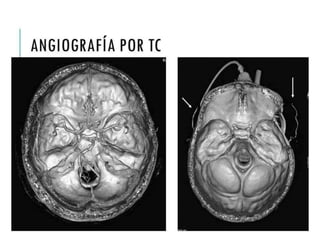

ANGIOGRAFÍA POR TC

Angiografía por TC Sensibilidad baja